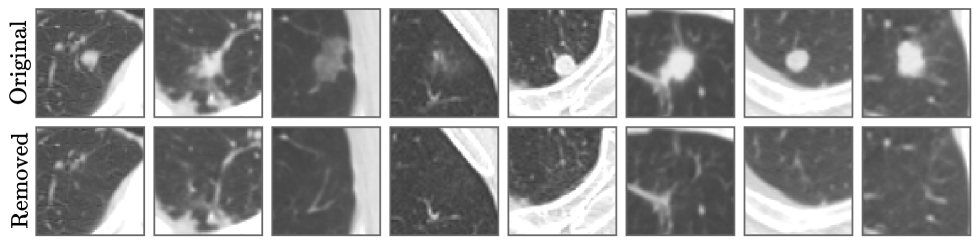

Examples of both nodule removal and insertion procedures are visualized in fig. 2, while broader literature context is provided in section A.5.

Nodule removal. Let be the LDCT training distribution for and be a counterfactual distribution where a specific nodule (within mask ) is replaced with healthy tissue via a do-operator (Pearl, 2009). Applying theorem 4.1 to their forward evolution up to , the distinguishing information within vanishes. SDB guarantees this erasure, as its dynamics converge to a state defined entirely by the masked region at . Since pulmonary nodules rarely exceed 0.1% of total lung volume (Horeweg et al., 2014), the score model effectively acts as a healthy tissue prior during reverse sampling, justifying this procedure for in-distribution nodule removal.

Nodule insertion. As anatomical anomalies linked to malignancy, nodules are unlikely to be generated by an unconditional model. To insert them, we define as a copy of where a nodule from a different patient is transplanted into mask and aligned with the new context. Theorem 4.1 implies and become statistically indistinguishable at some specific timestep . In practice, we simulate by ”copy-pasting” a specific nodule prior to diffusion. The theorem guarantees that at , the trained score model treats the diffused state as a valid sample from , allowing the reverse process to coherently integrate the inserted nodule into the surrounding anatomy.